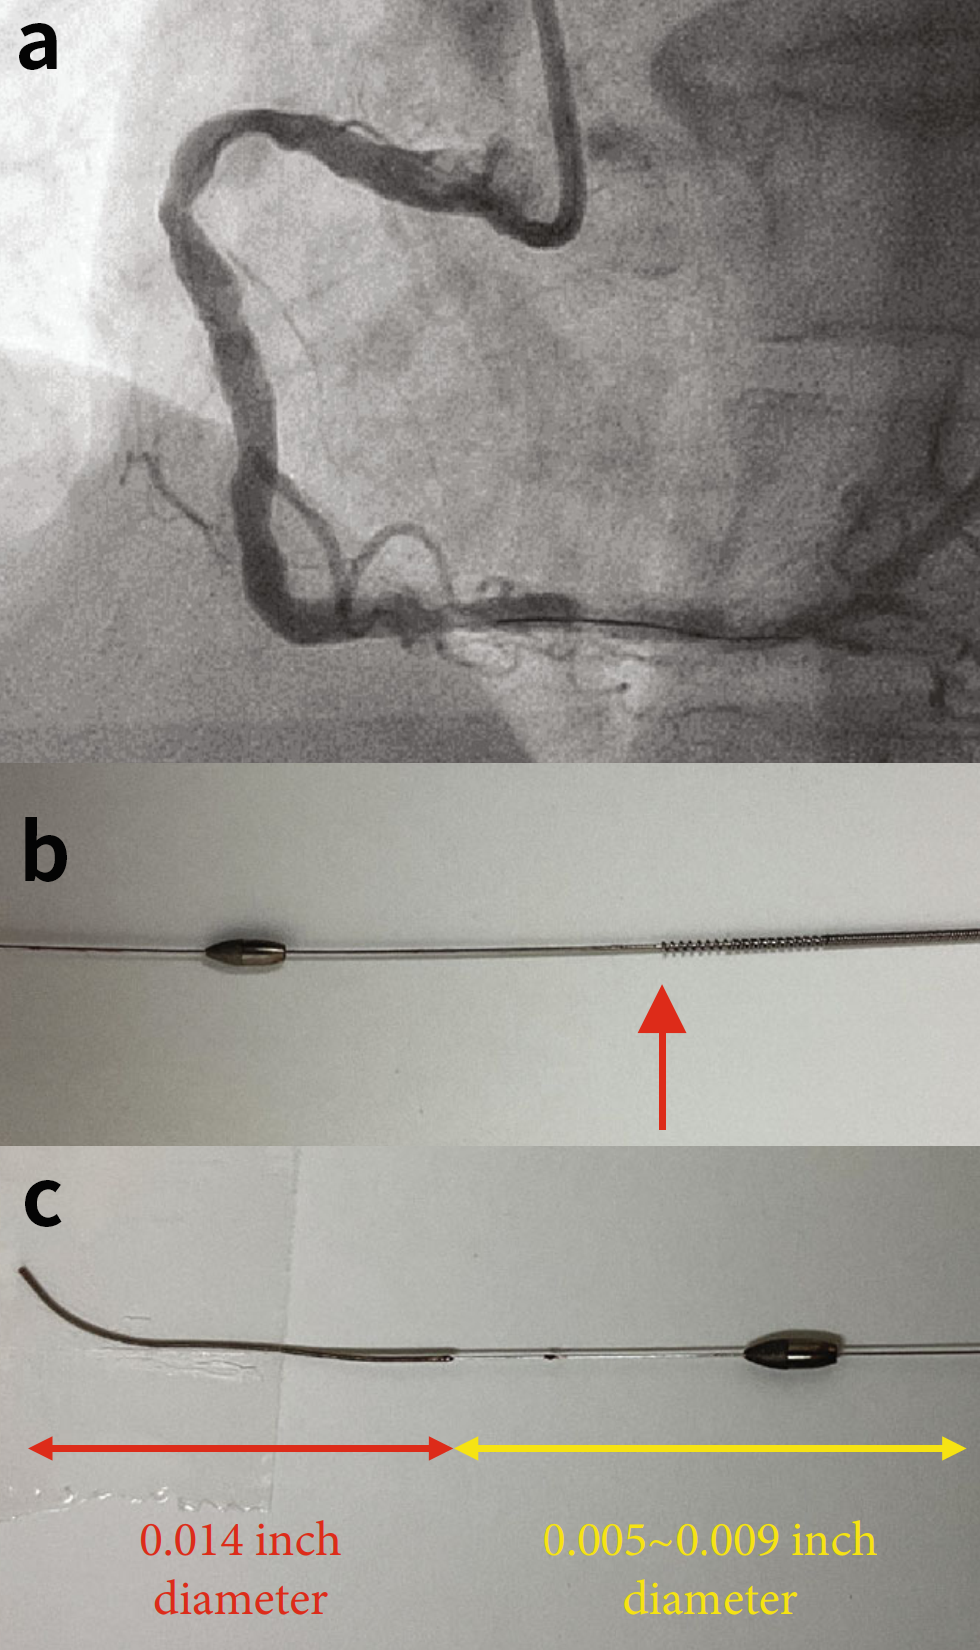

图2. (a)最终冠状动脉造影。(b)断开的旋磨头和驱动轴的边缘(红色箭头)。(c)旋磨导丝的远端和主体部分。

将另一根导丝从第二根指引导管中推送至RCA远端,并使用IVUS观察磨头。旋磨头并没有被困住(图3(a))。随后,使用旋磨导丝头端作为类似于绳结的锚点,将向RCA近端拉拽,这得益于旋磨导丝头端的0.014英寸直径(译者注:旋磨导丝头端直径0.014英寸,体部0.009英寸)。然而,旋磨头被卡在RCA中段狭窄的钙化部位内。

为了应对磨头杆断裂,在推进器附近切断了驱动轴护套、驱动轴和旋磨导丝,并将驱动轴护套拉出。尝试将圈套器推进至旋磨头处但未成功。沿着旋磨导丝将一根6Fr延长导管向磨头近端推进。然而,延长导管未能通过近端狭窄。因此,使用2.5mmNC球囊通过第二根引导导管对RCA近端进行扩张,随后对旋磨头滞留部位进行扩张(图3(b))。然后,推进延长导管,直到其与磨头接触,并将它们及旋磨导丝一起拉出(图4(a)),成功取出磨头(图4(b))。最后,在RCA中部植入4.0/15mm支架,并使用药物球囊对RCA近端进行扩张,完成治疗(图2(a))。

图4. (a)推进延长导管,直到其头端接触到。然后将延长导管、旋磨导丝和磨头一起拉出。(b)成功将旋磨头拉入到指引导管中取出。

在本例中,使用0.014英寸的旋磨导丝头端作为绳结锚点,成功将近端断开的磨头拉出(见图2(c))。针对磨头被卡住的情况,已有多种介入补救方法被报道。包括手动拉回旋磨导丝、在卡住区域反复扩张球囊、使用圈套器、深插指引导管以及使用延长导管等。